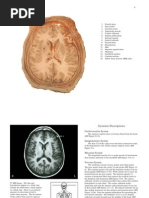

MULTIPLE SCLEROSIS (MS)

MS is a chronic inflammatory disorder of the CNS. There are multiple plaques of

demyelination within the brain and spinal cord. Plaques are disseminated both in time

and place.

Pathology

Plaques of demyelination, initially 2-10 mm in size, are the cardinal features.

Plaques are perivenular with a predilection for distinct CNS sites: optic nerves, the

periventricular region, the brainstem and its cerebellar connections and the cervical

cord (corticospinal tracts and posterior columns).

1. MRI of brain and cord is the definitive structural investigation. And shows

lesions in 85% cases with clinical M.S

 the periventricular region

 corpus callosum

 cerebellar peduncles

 juxtacortical posterior fossa

 Brainstem and cervical cord. Lesions are elliptical in shape with discrete

borders and lack of a mass effect. Typical lesions are multifocal (2 mm to 2

cm), with 10 or more lesions. Gadolinium can enhance active lesions. Plaques

are rarely visible on CT.